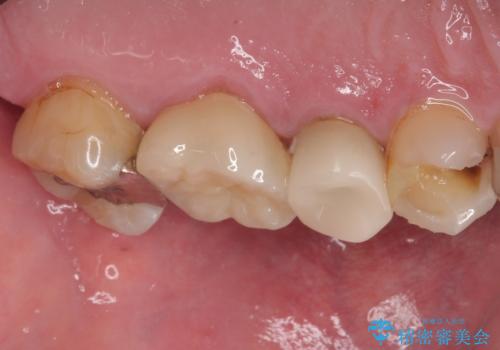

歯と歯の間の虫歯をコンポジットレジンや保険のメタルインレーで治すと段差ができたりして清掃性が悪くなるので、セラミックインレー修復やゴールドインレー修復などの適合の良い詰め物で治療することをオススメします。